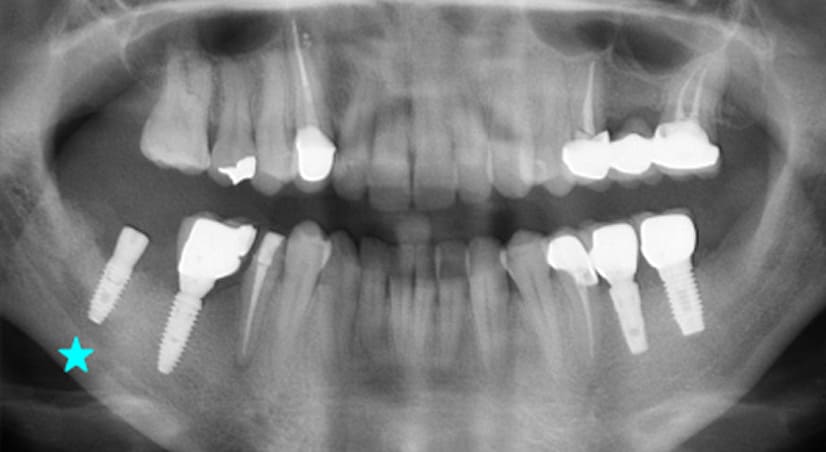

13+ 年

-

种植体植入:2012 年 9 月 -

最终修复体:2013 年 1 月 -

随访:13 年(2025 年 1 月)